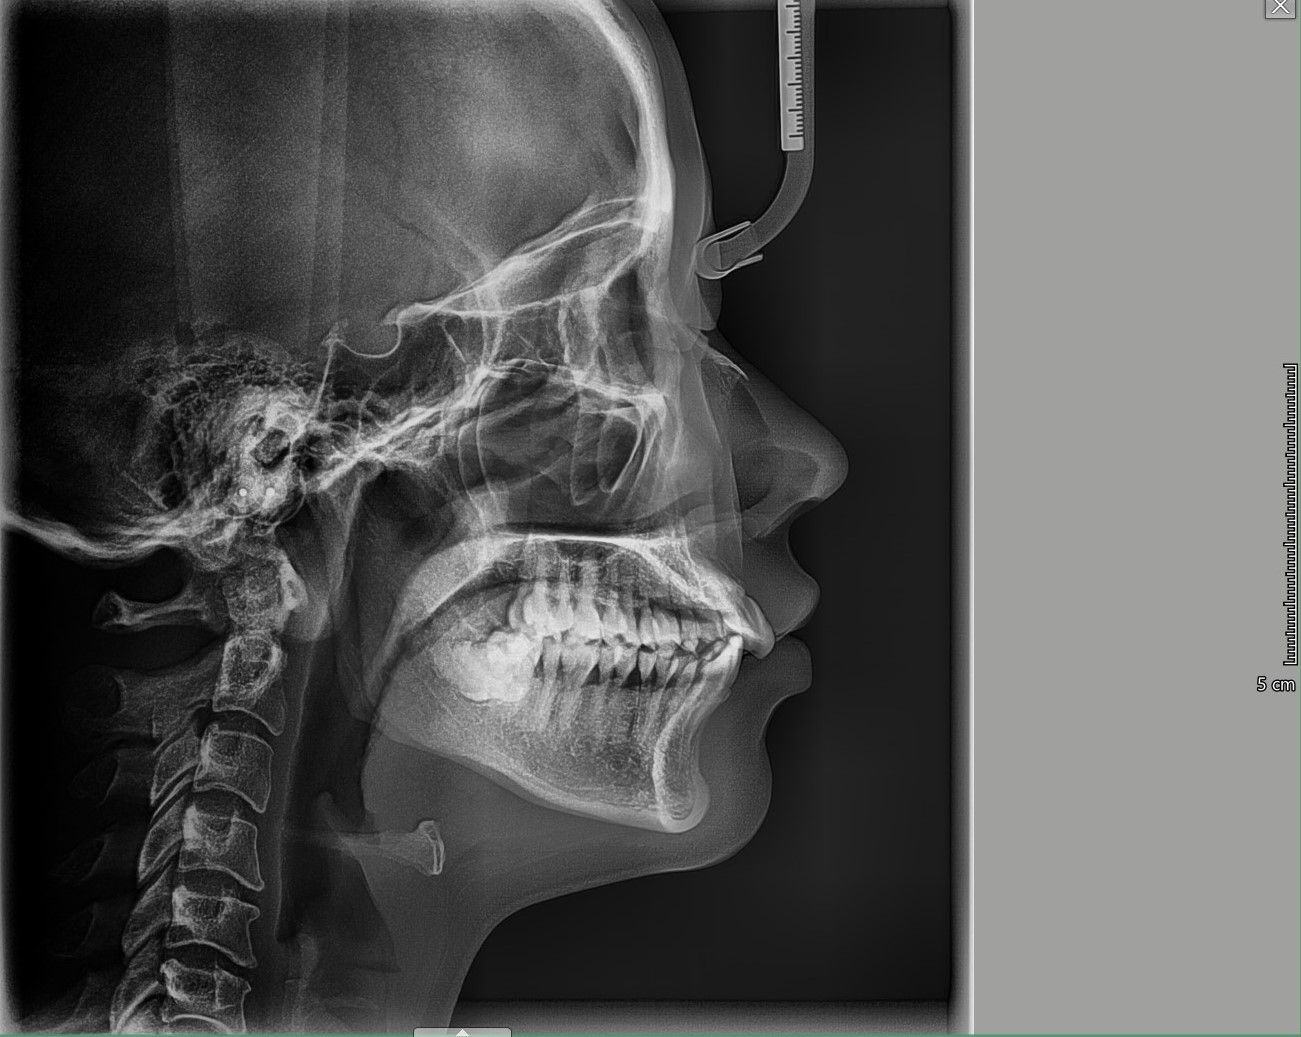

Nên niềng mắc cài hay invisalign cho tình trạng răng khấp khểnh vùng răng cửa, hô ở mức trung bình

Xin chào các bác sỹ Em đã đi tư vấn, các nha khoa đều đưa ra 2 lựa chọn mắc cài hoặc invisalign. Vậy em xin hỏi với trường hợp của em, phương pháp nào tối ưu, hiệu quả, tiết kiệm thời gian và an toàn hơn? Em cảm ơn.

Có thể khắc phục được tình trạng răng chen chúc xô lệch mà không cần nhổ răng không?

Tôi 23 tuổi và đang cân nhắc đến việc niềng răng để khắc phục tình trạng răng mọc khấp khểnh. Tôi đã đến gặp hai bác sĩ nha khoa thẩm mỹ và họ đều nói là cần phải nhổ răng nhưng tôi lại không muốn vậy. Hàm dưới của tôi gần như hoàn hảo nhưng tôi có tật nghiến răng vào ban đêm. Vậy tôi muốn hỏi là có thật sự cần phải nhổ răng hay không?